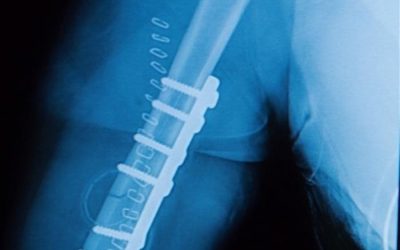

When Does a Rod Help After a Fracture?

Stabilizing the Break: How Rods Help Fractures Heal Did you know that 6 million people break a bone every year in the United States? You can break any bone, but the most common fractures occur in the: Forearm Wrist Ankle Hip Shin Collarbone Spine But no matter which...